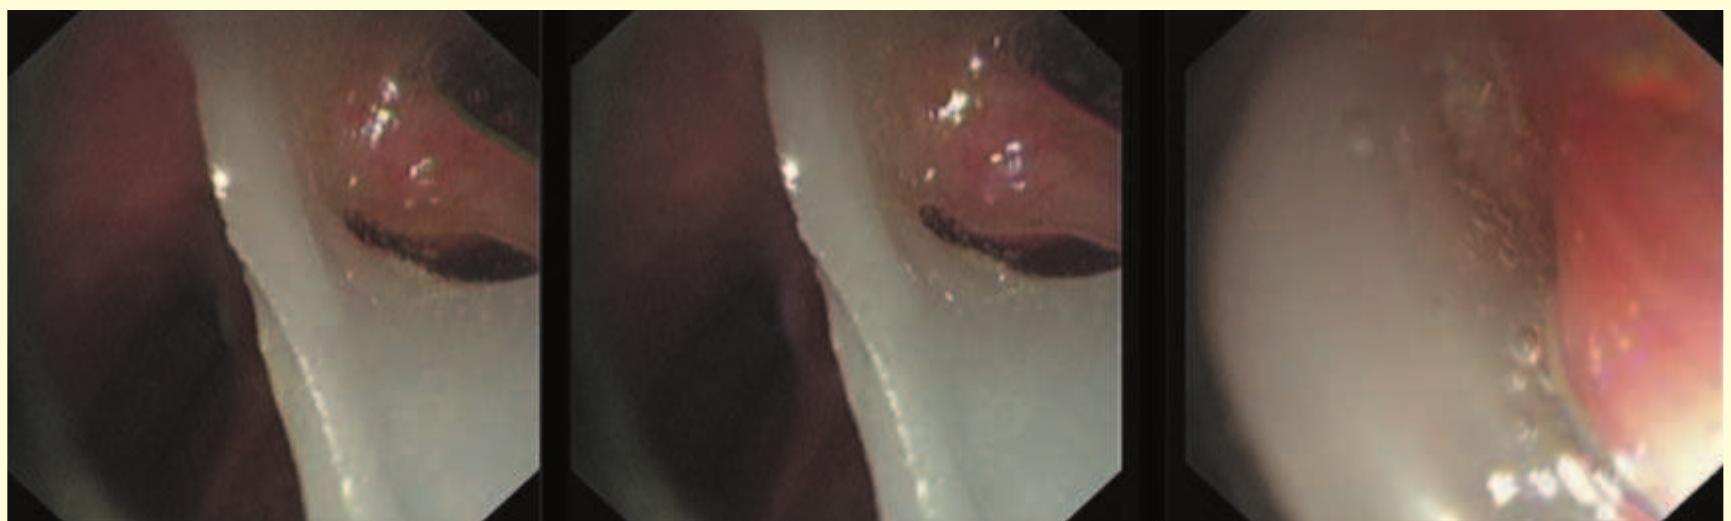

- Once the loop is tightened around the bronchoscope, the endobronchial blocker can be guided to any lobar bronchus (Fig. 12.11).